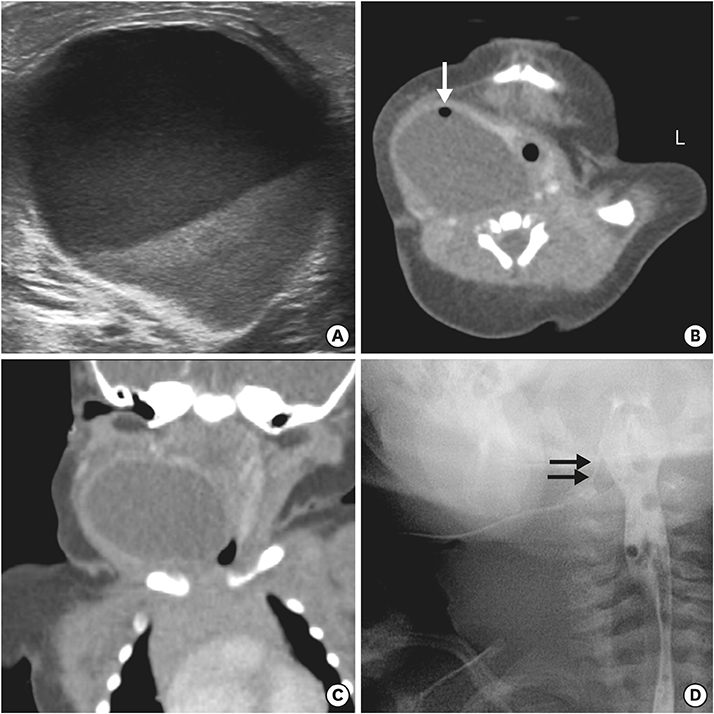

An otherwise healthy girl born at gestation age of 37+6 weeks, birth weight of 3.74 kg, delivered by Cesarean section was referred to our neonatal intensive care unit (NICU) 4 days after birth with swelling and redness of right neck. At birth, skin tag of the right chin was noted. Swelling and redness of the right neck started 2 days after birth. She was fed with normal formula, about 40 mL two to three times per day. She presented with high fever of 39°C and slight inspiratory distress during feeding. Physical examination showed a firm round mass of 4 cm diameter at the anterolateral aspect of right neck. Initial lab results showed nonspecific findings except increased C-reactive protein levels. Initial ultrasound (US) revealed a 3.6×6.5 cm sized elongated cystic mass, medial to carotid space, lateral to trachea, and extending to the retrothyroidal region, containing fluid level and surrounded by an irregular thick wall with minimal soft tissue infiltrates (Fig. 1A). Computed tomography (CT) showed air-bubbles in the nondependent portion of the mass with anterior displacement of trachea and right thyroid gland (Fig. 1B and C). Based on these findings, the mass was suspected to be a complicated anaerobe infected cystic hygroma. Antibiotics therapy were started and needle aspiration was done. Aspirated cystic fluid was yellowish and turbid. Streptococcus viridans was cultured from the fluid (Fig. 2A). Analysis of the fluid showed white blood cell count of 172,800 and low levels of total cholesterol and triglyceride. Feeding was initiated from postoperative 1 day, and size of the cyst started to increase rapidly after needle aspiration, returning to its previous size within two days. Excision of the cyst was done on the 7th day of hospitalization (Fig. 2B). Feeding was reinitiated on postoperative day 1. Pus discharge drained from the neck wound on postoperative 4th day and it contained milk-like substance right after feeding. Esophagography was performed on postoperative day 8, revealing a hairline fistulous communication from the right pyriform sinus to the cyst, suggesting a pyriform sinus fistula due to 4th branchial cleft anomaly (Fig. 1D). Once gastric tube feeding was initiated, size and drainage from the cyst started to decrease. A follow-up esophagography after 15 days demonstrated obliteration of the fistula tract and bottle feeding was started. She was discharged from the hospital after 1 week of bottle feeding, showing no signs of recurrence.

Fig. 1

(A) Ultrasound and (B, C) computed tomography images revealed a 3.6×6.5 cm sized elongated cystic mass, containing fluid level and air bubble (white arrow). (D) Fistulography shows a faintly opacified hairline tract (black arrows) originating from the right pyriform sinus.

Air bubbles in the inflammatory cavity of pyriform sinus tract may be due to production of air-forming bacilli or inhaled air from opening of pyriform sinus tracts [6]. These air bubbles may be noted on US, CT or MRI findings, and also on close observation of initial plain X-rays. In our first case, air bubble was not found on US but was visualized on the neck CT. At first, we assumed it to be air-fluid level within an abscess formed by anaerobic bacterial infection and treatment was targeted toward infection based on the assumption of complicated infected cystic hygroma. Earlier acknowledgement of the possibility of air inflow from an open sinus tract would have accelerated the process of correct diagnosis.